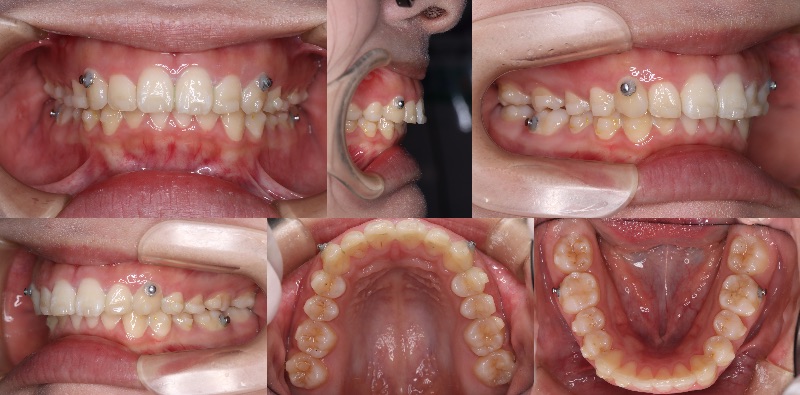

smartee症例のアタッチメント脱離についてご相談させてください。

Cくん 男児

現在9ステージ目使用中です。

他の症例では問題なく経過しておりますが、

本症例に限っては、

装着から約2週間で毎回ほとんどのアタッチメントが脱離している状態です。このままでは計画通りの進行が難しいと感じております。

現在の装着手順は以下の通りです。

・歯面研磨:メルサージュ使用

・エッチング(EE)、ボンディング(EB)実施

・アタッチメントテンプレート使用

・フローレジン:オムニクロマ使用なお、現在は9ステージ目まで進んでおりますが、

進捗への影響も懸念されるため、

再スキャンが必要な場合はご指示いただけますと幸いです。つきましては、以下についてご教示いただけますでしょうか。

① 小児症例特有の脱離リスク(エナメル質の性状など)の影響について

② 材料選択(オムニクロマ)の適否

③ 小児における有効な接着手技のポイント

④ 咬合干渉や生活習慣(咬み癖など)の影響の考え方本症例のみで起きている現象のため、

個別要因が強いのではないかと考えております。口腔内写真

〇アタッチメント取れなかった

×アタッチメントダツリお忙しいところ恐縮ですが、

ご教示のほどよろしくお願いいたします。 -